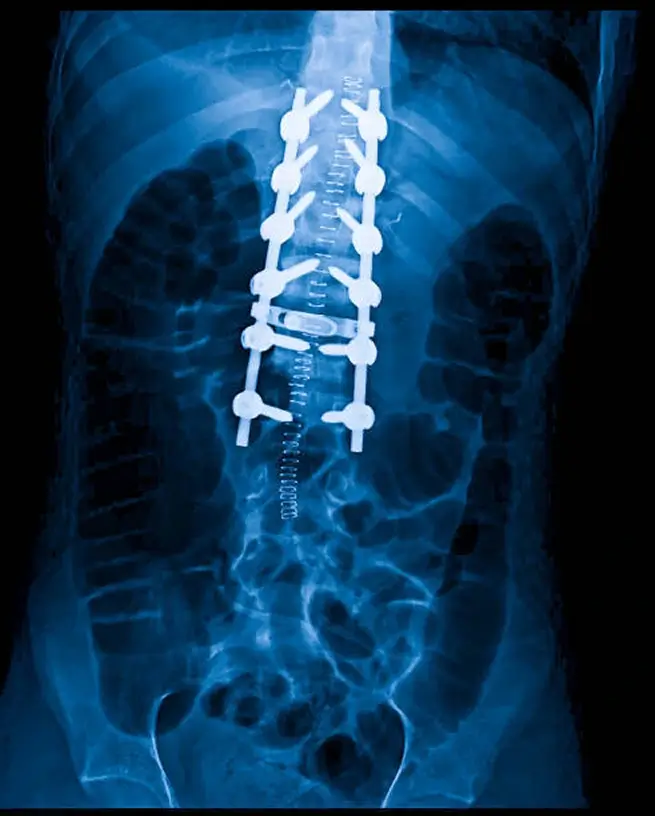

A surgical technique known as Spinal Fusion is used to treat these disorders. Metal screws, rods and cages are used to fuse together two or more adjacent vertebrae. The aim is to stabilize the spine and stop the motion of spinal vertebral segments, and to relieve pain by eliminating pressure on the spinal cord or on the nerve roots.